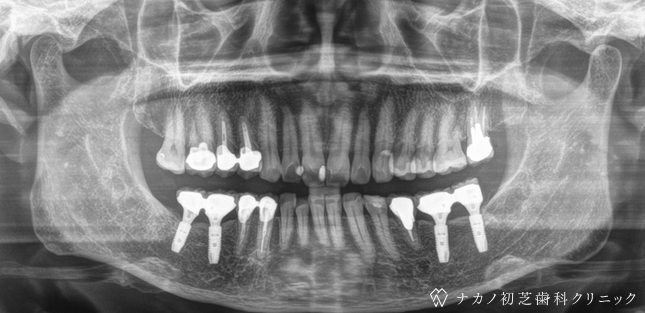

インプラント・6本 (50代男性)

BEFORE

AFTER

年齢 50代男性

治療内容 インプラント治療6本(骨造成の併用)

インプラント治療とは、歯を抜いた所にチタン製の人工歯根を埋入し、その上に歯を入れる方法です。骨を増やすことで、より審美的に治療が出来ました。費用 1本 400,000円(税込 440,000円)

リスク・副作用

腫れ・疼痛・違和感を感じるなどの症状を生じることがあります。